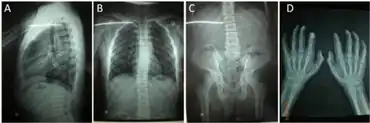

MLIII a,b) Mild hyperlordosis of thoracic/lumbar spine c) joint stiffness of hip. d) normal in length/width